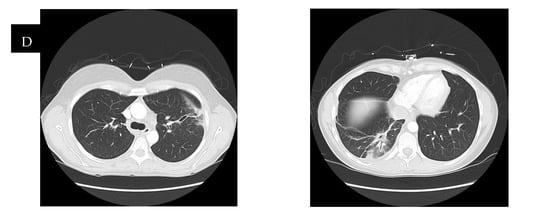

Radiological findings continue to be a mainstay in the diagnosis of necrotizing pneumonia. However, chest X-rays often are not sensitive enough to make the definitive diagnosis of necrotizing pneumonia or to differentiate it from other causes, such as lung abscesses. Bulging fissures may be an early radiographical sign, indicating the extensive inflammation that occurs [3]. A CT with contrast is the optimal imaging modality as it enables the appreciation of areas with low attenuation and decreased enhancement, which are compatible with necrotizing lesions. In contrast to pulmonary abscesses or gangrene, which tend to be isolated to one lobe, necrotizing pneumonia more frequently is multi-lobar in nature and has more extensive airway disease [3,17]. The right middle and lower lobes are most commonly affected in imaging [25]. The presence of micro-abscesses can be used to distinguish necrotizing pneumonia from other conditions causing parenchymal lucency. Significant overlap continues to exist between radiographical findings of necrotizing pneumonia and pulmonary gangrene. Many sources use the extent of lobe involvement as a distinguishing feature, with the term pulmonary gangrene being used when greater than 50% of the lobe is affected [26]. (See Figure 2).

Figure 2.

CT scans of a patient with necrotizing pneumonia and progression through time, with row (D) representing images after the completion of treatment. The time between images in row (A) and row (D) is six weeks. Row (B,C) represent CTs that were taken in between the time of row (A) and row (D), showing the progression of improvement.